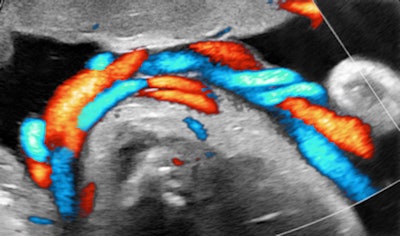

I recalled that case when I saw a primipara at 34.6 weeks, sent in because of suspected growth acceleration. A second-trimester exam had shown a normal-appearing male fetus and established the dating. The unexpected finding was a double-loop nuchal cord with some lengthy segments of diminished spiraling of the arteries. Multiple loops are generally thought to convey an increased chance of complications.

All images courtesy of Dr. Jason Birnholz.

There are high-velocity spicules in the tracing. We have tended to think of these as microturbulence events, signaling the presence of surfactants in ejected lung fluid. This is unusual at the current gestational age in a male fetus, except when there has been repeated stress promoting lung maturation.We hit the panic button when we observed a lot of exaggerated head and torso movements (like aversive behavior) with a lot of mouth and tongue activity. I will leave it to you to decide what to make of fetal expression during one of the movement episodes.